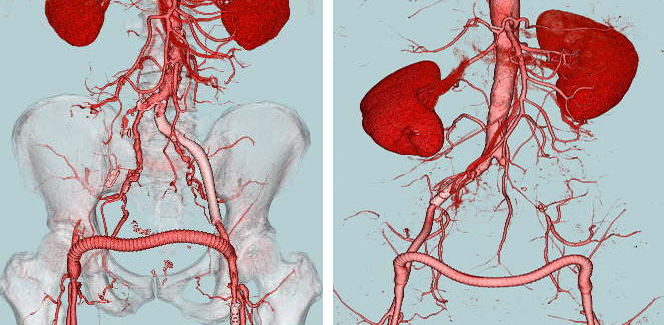

- 高位大動脈閉塞(Leriche synd) 【写真】

- 腸骨動脈完全閉塞(右) 【写真】

- 腸骨動脈狭窄 【写真】

考え方としては、早期であるほど2の血管内手術のみで治る可能性が高いと考えてよいでしょう。現在の末梢動脈に対する血管内手術の適応は、大動脈・腸骨動脈領域から膝下動脈、さらに足関節から足趾にまで及びます。しかし、それぞれの治療法には当然ながら適応があります。このためしばしば従来からの手術との組み合わせであるハイブリッド手術が必要になりますが、血管内呪術の関与する割合は8~9割にも及んでいます。